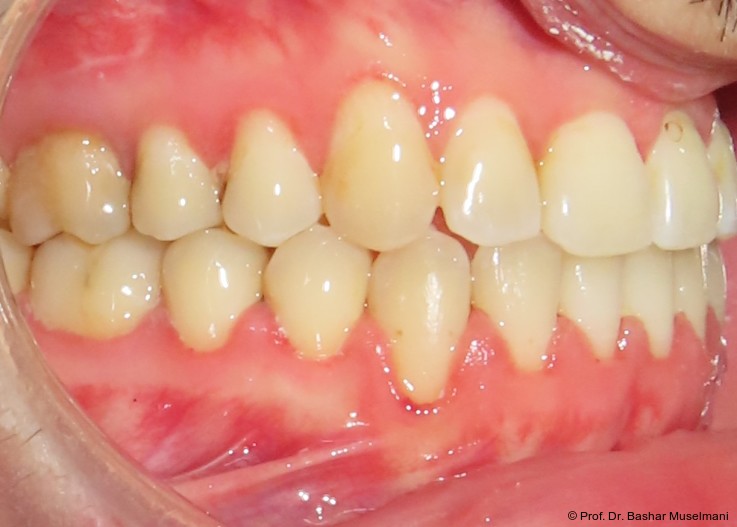

Der Patient (28 Jahre 8 Monate) stellte sich mit einer skelettalen Klasse III sowie einer Mittellinienabweichung nach links vor.

Klinische Befunde

• leicht konkaves Gesichts- und Mundprofil

• posterior positionierter Unterkiefer (VW)

• retroinkliniert stehende Unterkieferfront

Die Abbildungen 1 bis 3 zeigen die initiale klinische und radiologische Ausgangssituation.